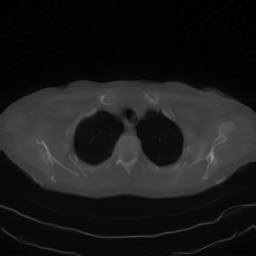

A qualitative comparison can be carried out by examining Figures 2, 3, and 4, which show the reconstructions with the zoomed region identified by the red square. The figures confirm the results reported in the tables, as the reconstructions obtained with DPS and DiffPIR contain noticeable errors. In particular, the DiffPIR reconstruction appears highly blurred and poorly defined. With respect to the images obtained using the two best-performing methods reported in the table, namely DDRM and RD-DGP, we observe that the resulting images exhibit different characteristics. In particular, the reconstructions of image C081-35 (Figure 2) appear quite similar for both methods, In contrast, for images C081-45 and C081-79, inspection of the cropped regions shown in the figures reveals that the DDRM reconstruction exhibits incorrect object shapes, whereas this effect is substantially less pronounced in the RD-DGP reconstruction. Additionally, DDRM images appear more contrasted but also noisier.

Figure 2: Visual comparison of different reconstruction methods for Sample C081-35 across three sparse-view configurations (nα=30,45,60n_{\alpha}=30,45,60). The red box indicates the zoomed region shown in the inset.